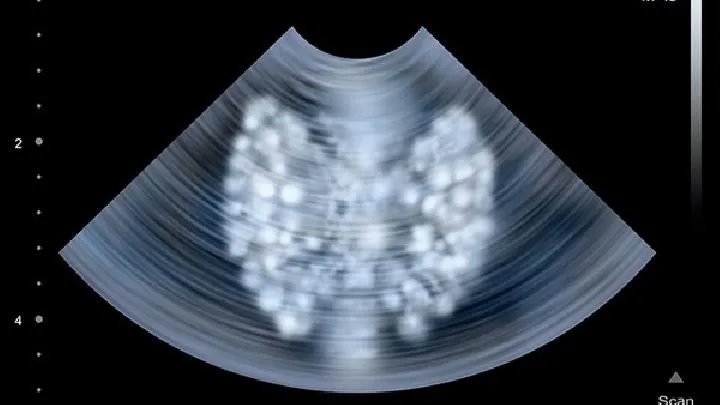

的有关信息介绍如下:心脏移植,就是将捐献者提供的(供体)健康心脏植入到接受移植的患者(受体)的胸腔或其他部位,部分或完全地替代受者的心脏,以维持受体循环功能的稳定,从而达到延长生命、改善生活质晕的目的。

根据心脏被移植到人体的部位,又可分为原位心脏移植和异位心脏移植。其中,原位心脏移植是指病心被切除后,在心脏的原来位置植入另一个心脏。而异位心脏移植则是不切除病心,将另一个心脏植人到人体其他部位,通常为胸腔内。